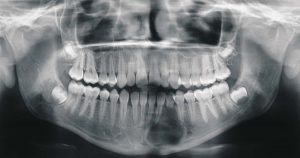

1. Panoramic X-rays – More specifically known as orthopantomogram or OPG, this is a device that rotates around the head of the patient to provide an image of the teeth in relation to the jaws. The orthopantomogram shows both the upper and lower jaws and the entire bone structure in one picture. OPGs often demonstrate the position of the developing teeth; more importantly, they also assist in identifying tumors, impacted third molars, or any other irregularity occurring in the jaws.